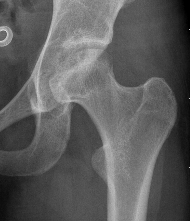

Xray

Stage II: sclerosis with cystic areas resorption, no collapse